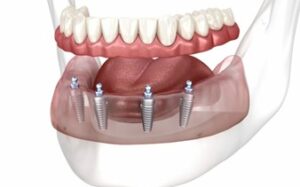

All-on-Four implants is a revolutionary dental implant technique designed to replace an entire arch of missing teeth (either upper or lower) using just four dental implants. These implants act as strong anchors that support a fixed prosthetic bridge, providing a stable and permanent set of teeth.

Unlike traditional implants, where each missing tooth may require an individual implant, the All-on-Four technique uses four implants positioned in specific angles to maximize bone support. This method often eliminates the need for bone grafting, making the procedure faster and more convenient for many patients.

During the procedure, four titanium dental implants are surgically placed into the jawbone. Two implants are placed vertically at the front of the jaw, while the other two are angled toward the back to provide maximum stability.